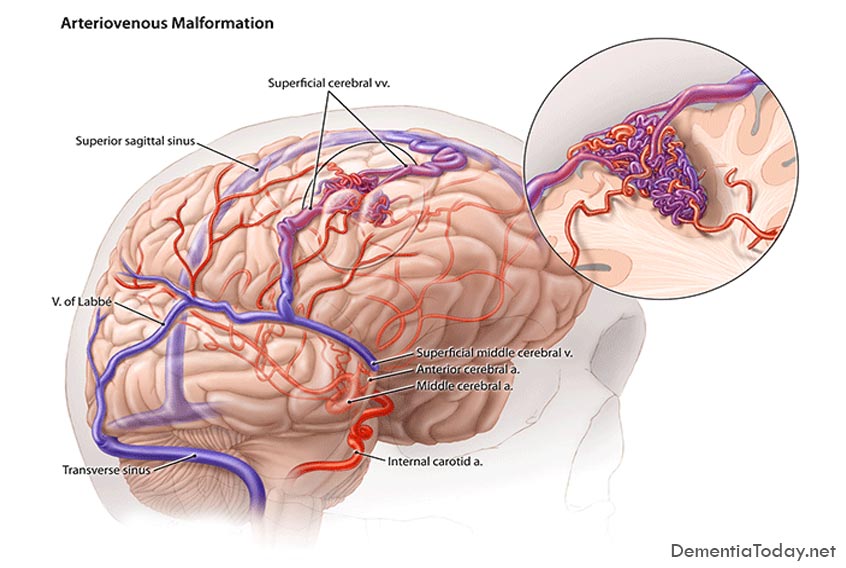

Мр картина венозной ангиомы левой гемисферы мозжечка - 96 фото